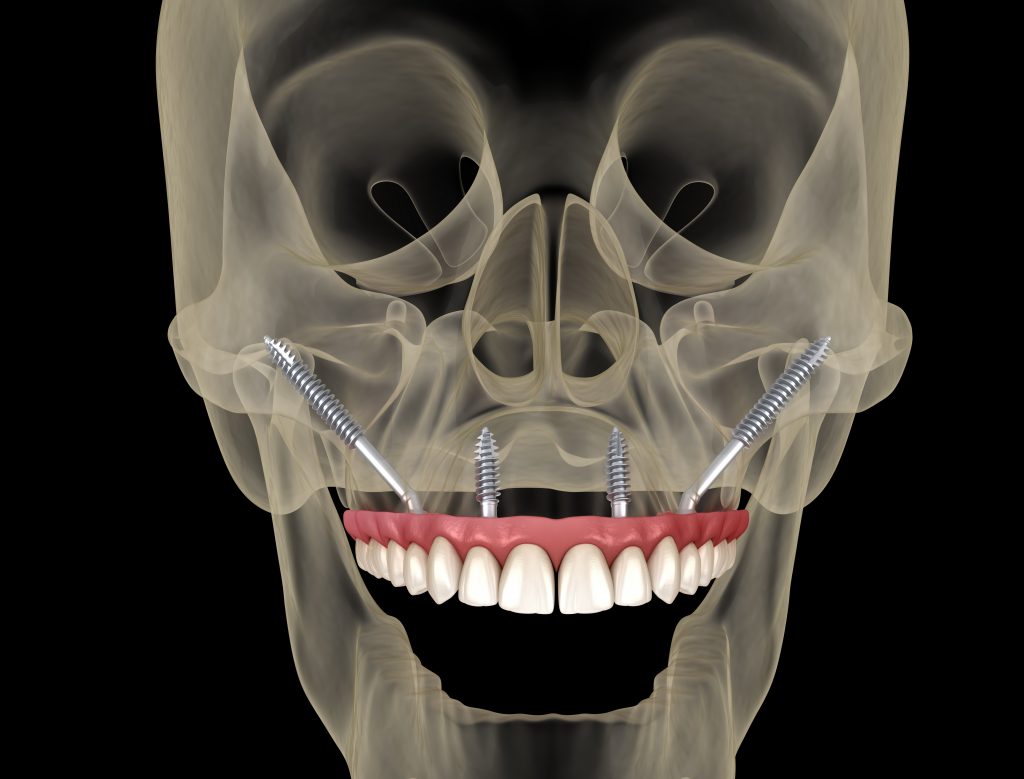

Los implantes cigomáticos son un tipo de implante dental especialmente diseñado para pacientes que no tienen suficiente hueso en el maxilar superior. A diferencia de un implante convencional, que se fija en el hueso del maxilar, el implante cigomático es más largo y se ancla en el hueso cigomático (el pómulo), una zona muy densa y estable que siempre mantiene suficiente estructura ósea, incluso cuando el maxilar está muy reabsorbido.

El número de implantes cigomáticos necesarios suele variar entre 1 y 4 por arcada y depende principalmente de la calidad del hueso maxilar y la calidad del hueso cigomático (pómulo). Cuando el hueso del maxilar no es suficiente, utilizamos el hueso cigomático (el pómulo) como punto de anclaje.

Si la pérdida ósea solo afecta a una parte del maxilar, es posible colocar un solo implante cigomático en la zona con peor hueso y completar el resto de la sujeción con implantes tradicionales, que es una cirugía más sencilla y más económica.

Sin embargo, cuando no existe buen hueso maxilar en ninguna zona, o incluso cuando el punto de apoyo en el pómulo no ofrece la estabilidad ideal, pueden necesitarse hasta 4 implantes cigomáticos para conseguir una fijación segura y permitir una rehabilitación fija inmediata.

Un implante cigomático mide entre 35 mm y 55 mm, mucho más que un implante dental convencional, que suele medir entre 8 y 18 mm. Su longitud permite alcanzar el hueso del pómulo para ofrecer la estabilidad necesaria en casos de atrofia ósea severa.